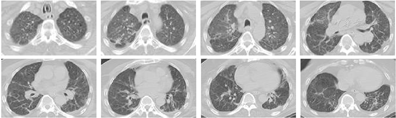

8月12日再次复查胸部CT见双肺渗出较前已基本吸收(图3)。8月18日脱离呼吸机,仅给予低流量氧疗,复查动脉血气:PCO2 51.8 mmHg,PO2 76.0 mmHg。8月20日转呼吸科。